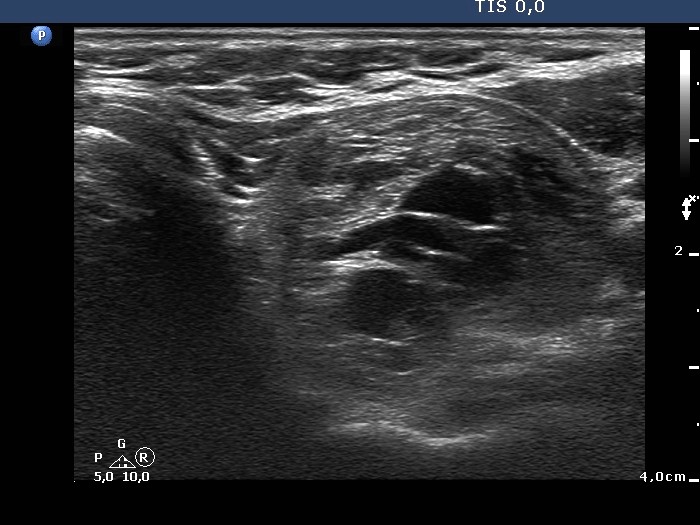

Benign cystic lesion (cytological diagnosis) - case 1139

The posterior acoustic enhancement in the dorsal wall of the small cystic areas causes no concern if this optical artifact is linear (arrows), however granular figures might be misinterpreted as punctate echogenic foci (microcalcifications) (arrowheads).